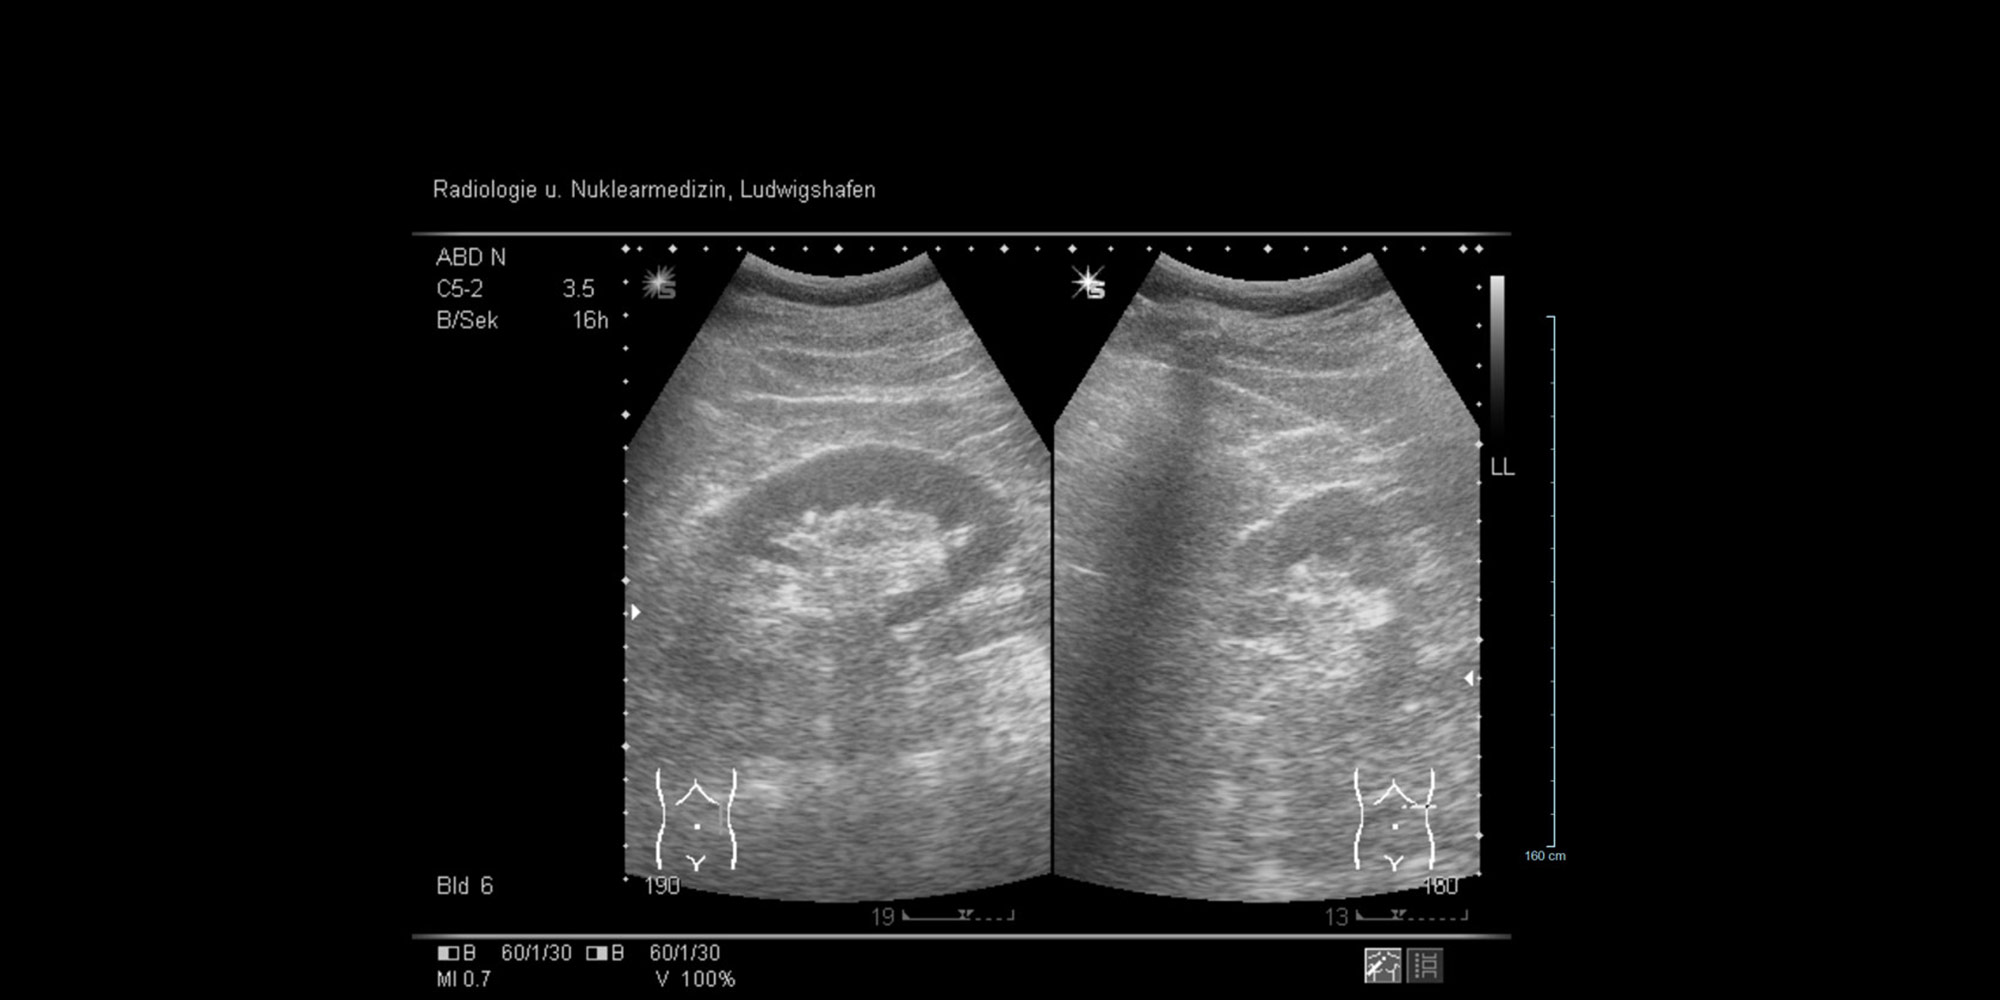

Das Prinzip der Sonographie beruht auf der Anwendung von Ultraschallwellen im nicht hörbaren Bereich. Der untersuchende Arzt erhält zweidimensionale Direktbilder, die ihm über einen Monitor eine Vorstellung von Größe, Form und Struktur des untersuchten Bereiches geben.